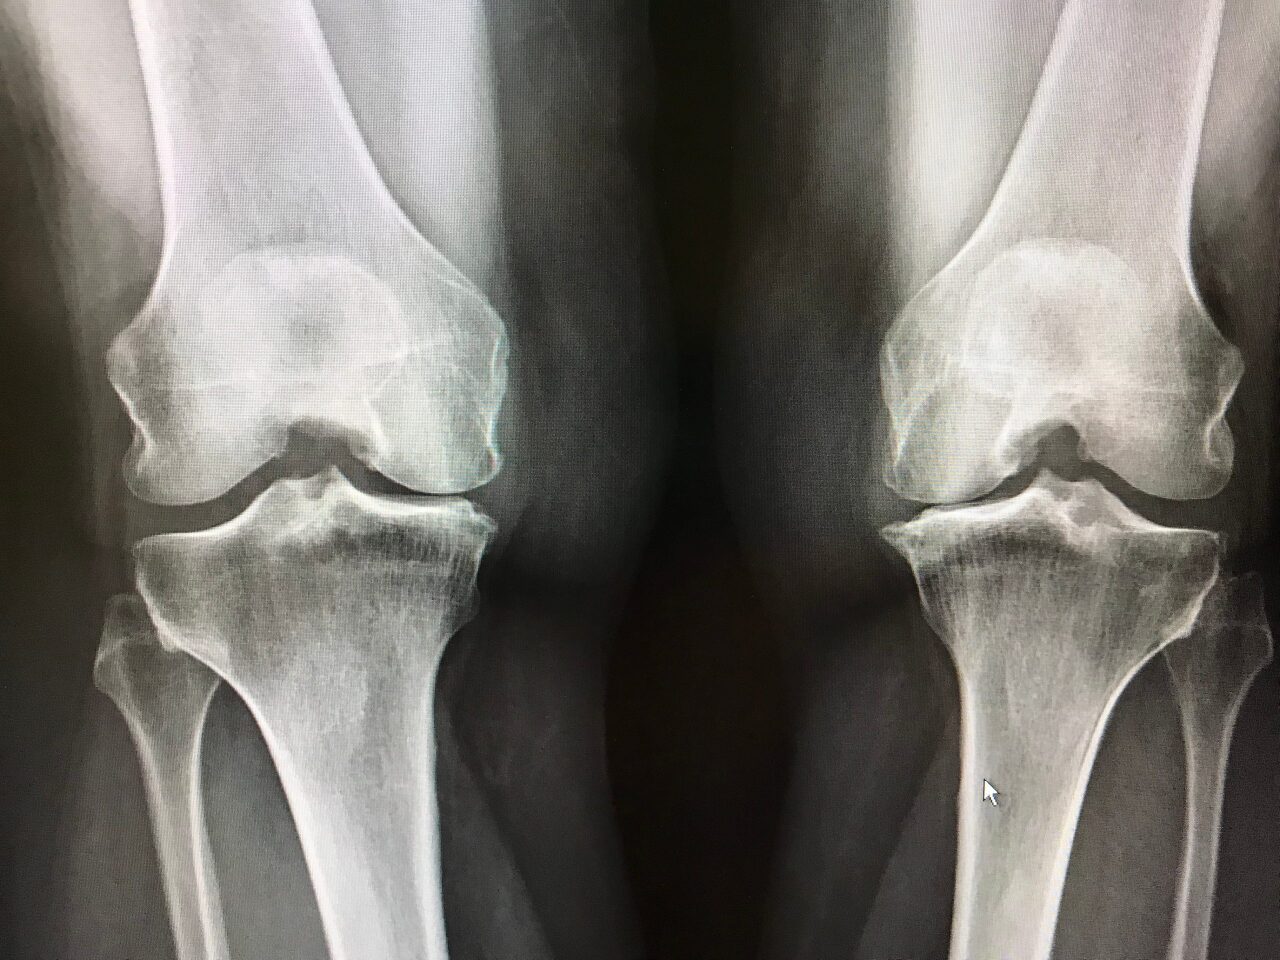

퇴행(degeneration)

- 닫혀진 무릎관절 (Knee joint space)

- 양측으로 발생된 골극(spur)